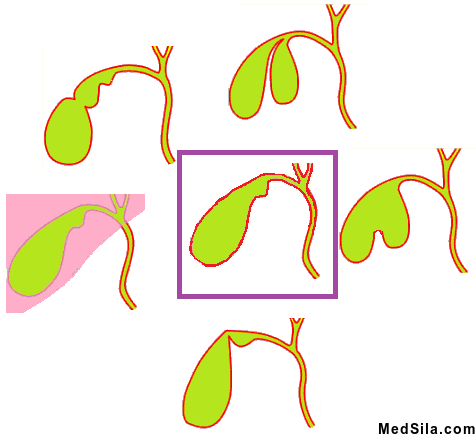

- Застой желчи в пузыре, что чаще всего обусловлено аномалиями строения пузыря (перегибы, перетяжки) и дискинезии желчевыводящих путей (функциональные нарушения проведения желчи);

Все эти причины ведут к нарушению соотношения различных кислот и холестерина в желчи, что способствует выпадению холестерина в осадок с его последующим преобразованием в "камни". Сначала холестерин выпадает в виде хлопьев и на этом этапе, при нормализации образа жизни, не обязательно превращение «хлопьев» в конкременты (камни). А при продолжении влияния неблагоприятных факторов образуются «песок» или «камни» желчного пузыря. Камни могут быть мелкими и крупными, одиночными и множественными. Могут заполнять просвет на треть, половину или полностью заполнять просвет пузыря (такой желчный пузырь называется отключенным).